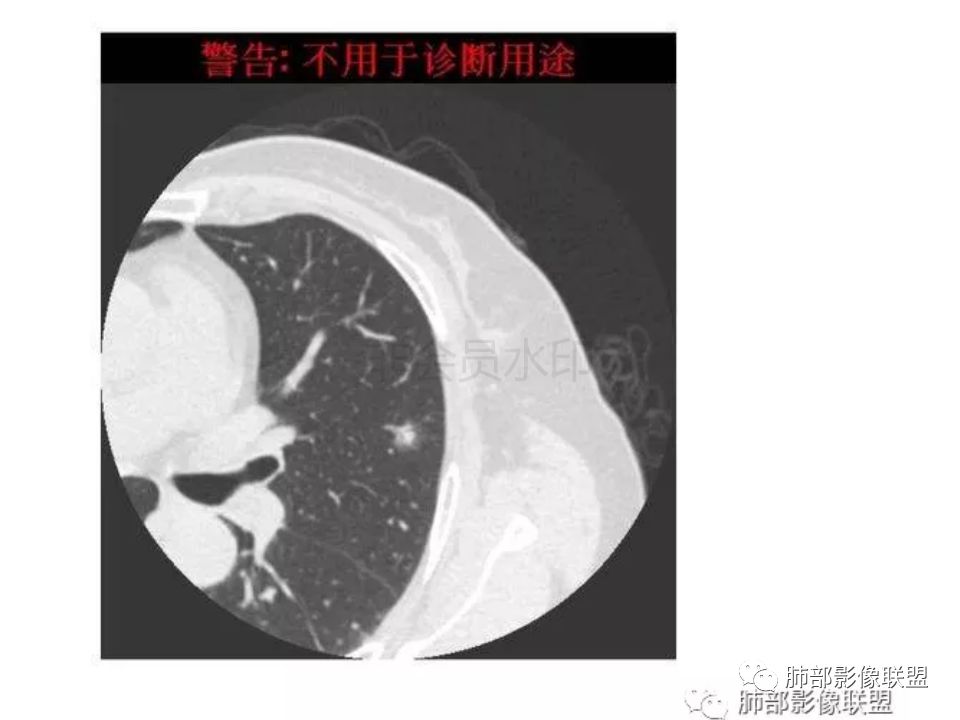

【每日晨读】腺癌VS隐球菌

隐球菌感染孤立病灶与肺腺癌结节在影像上有时难分彼此,尽管隐球菌胸膜下更常见。

1.隐球菌病灶往往是实性密度结节为主伴周边边界不清楚的晕,有时可见晕内细软毛刺。

2.隐球菌病灶形态往往圆钝柔和,缺乏收缩能力,很少出现腺癌的那种胸膜牵拉和棘状突起。

3.病灶内支气管安然无恙隐球菌病灶更加多见